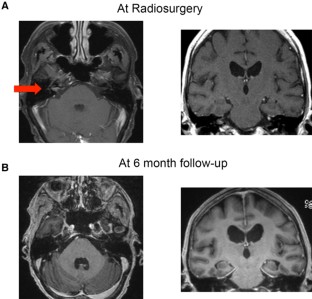

Leptomeningeal disease (LMD) is well described in patients with brain metastases, presenting symptomatically in approximately 5% of patients. Conventionally, the presence of LMD is an indication for whole brain radiation therapy (WBRT) and not suitable for stereotactic radiosurgery (SRS). The purpose of the study was to evaluate the local control and overall survival of patients who underwent SRS to focal LMD. We reviewed our prospective registry and identified 32 brain metastases patients with LMD, from a total of 465 patients who underwent SRS between 2013 and 2015. Focal LMD was targeted with SRS in 16 patients. The median imaging follow-up time was 7 months. The median volume of LMD was 372 mm3 and the median margin dose was 16 Gy. Five patients underwent prior WBRT. Histology included non-small cell lung (8), breast (5), melanoma (1), gastrointestinal (1) and ovarian cancer (1). Follow-up MR imaging was available for 14 patients. LMD was stable in 5 and partially regressed in 8 patients at follow-up. One patient had progression of LMD with hemorrhage 5 months after SRS. Seven patients developed distant LMD at a median time of 7 months. The median actuarial overall survival from SRS for LMD was 10.0 months. The 6-month and 1-year actuarial overall survival was 60% and 26% respectively. Six patients underwent WBRT after SRS for focal LMD at a median time of 6 months. Overall, focal LMD may be may be treated successfully with radiosurgery, potentially delaying WBRT in some patients.